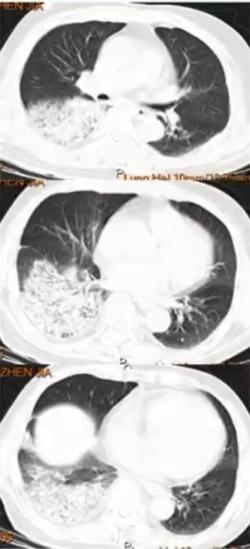

病例6

女性,14岁,学生。发热、咳嗽10天入院。

院外治疗经过

• 第1-3天:阿奇霉素治疗3天(口服2天+静脉1天)无效,胸片示左上肺及右下肺斑片影

• 第4-5天:头孢曲松+阿奇霉素+小剂量激素2天无效,肺CT示左上肺大片实变及右下肺斑片影

• 第6-7天:头孢曲松+阿奇霉素+甲泼尼龙40mg bid 2天仍无好转,出现呼吸困难,CT示肺内病变进一步增多,血常规7.8×109/L、N 82.9%,CRP 43.16 mg/L,动脉血气分析PH7.42 PaO246mg Hg。

• 第8-9天:美罗培南+利奈唑胺+甲泼尼龙 80mg/d,体温无下降,呼吸困难加重,吸氧8-10L/min,指脉氧80%左右,G试验154.7,加用伏立康唑,行气管插管机械通气,病情仍无改善转来我院。

院外病原学检查结果

• 痰涂片:偶见G+球菌 呈双排列

• 痰培养:少量假丝酵母菌

• CMV IgG 0.8AU/ml(<6),IgM 0.32(<0.85)

• 甲流及乙流抗原阴性

• 呼吸道病原九项IgM(包括嗜肺军团菌、肺炎支原体、肺炎衣原体等)均阴性

图6 患者在院外胸部影像学变化。左上肺小块实变,逐渐累积至右下肺,而且左上肺实变扩大和膨胀不全。

图7 患者入院当日病情小结

图8 患者入院当日胸部CT。左上肺大面积实变,右上肺斑片影,出现胸腔积液

病原学诊断

入院第1日:痰培养无菌生长;痰涂片:少量G-球菌,未见真菌;血培养:5天无菌生长(普通+厌氧);GM抗原:小于0.25μg/L;G试验:96.5pg/ml

入院第2日:BALF-mNGS:肺炎支原体;BAL涂片:未找到细菌真菌、未找到抗酸菌

入院第9日肺炎支原体抗体:>1:1280

治疗转归及误诊原因分析

①转归

美罗培南+米诺环素治疗48小时后退热;住院治疗第5天撤机拔管;住院治疗第10天停用美罗培南;米诺环素疗程共30天;住院34天出院。

②初始治疗失败原因分析

• 临床和影像表现不典型:实变、呼衰、高凝

• CAP常规初始经验性治疗无效:肺炎支原体大环内酯类抗生素耐药

• 缺乏肺炎支原体感染的早期诊断技术